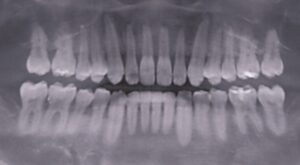

2年前からインビザラインして今月終了したが、上顎全体が前に出ているのと、下顎が後退しているのが気になる。

他に医院ではミニスクリューを勧められた。歯を抜かずに矯正しているため、イーラインが前に出ている。

4番抜歯をしないと治らない。しかも、奥歯が噛んでいない。ワイヤーによる全顎矯正が必要。